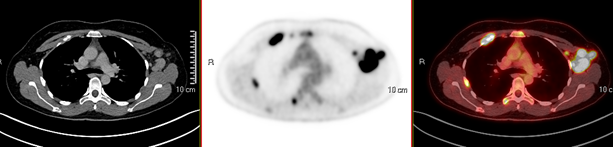

El estadio IV implica que el cáncer ha hecho metástasis a otros órganos, lo que requiere un enfoque de tratamiento más agresivo. La habilidad del PET/CT para identificar estos cambios es fundamental para los oncólogos, ya que facilita la decisión sobre el tratamiento, que puede incluir quimioterapia, radioterapia y cirugía, lo que depende del estadio y la diseminación del cáncer. “En las figuras 1 y 2” se observa un ejemplo de una paciente que acudió a la unidad, quien presentaba un estadio IIA antes del PET/CT y posteriormente cambió su estadiaje a IV, con metástasis a región axilar y ósea; contaba con subtipo molecular HER2 positivo, el cual se caracteriza por su agresividad, rápida diseminación a SNC y mal pronóstico.

Figura 2. Cortes axiales de CT, PET y PET-CT a la altura del mediastino superior. Se observa actividad tumoral metastásica en adenopatías axilares izquierdas, así como en estructuras óseas